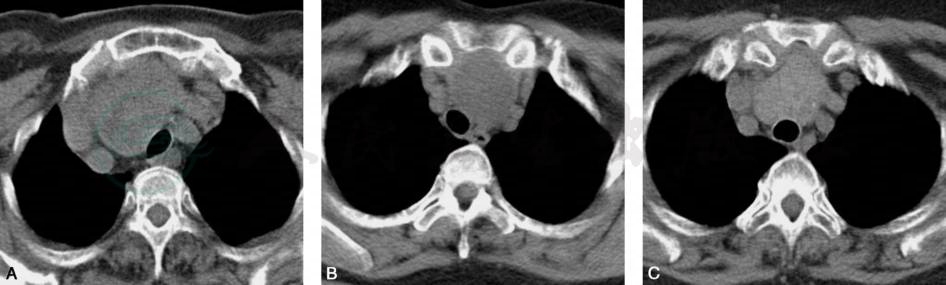

图1胸内甲状腺肿

A~C.不同层面CT横断面平扫图像,上纵隔可见囊实性病灶,与甲状腺右叶相连,实性成分较多,周围血管、气管受压移位

①多数病灶与颈部甲状腺相延续,位于气管前间隙内,亦可伸入到气管与食管之后方;②肿块缘光滑,密度多不均匀,伴单个或多个低密度区,常见点状或不规则钙化;③平扫肿块CT值高于周围肌肉组织,常为50~70Hu,有时可达110~130Hu,囊性区CT值15~35Hu,增强后实质强化明显,且持续时间较长,密度与正常甲状腺相仿略低;④多数病例纵隔大血管及气管有典型推移表现(图1)。